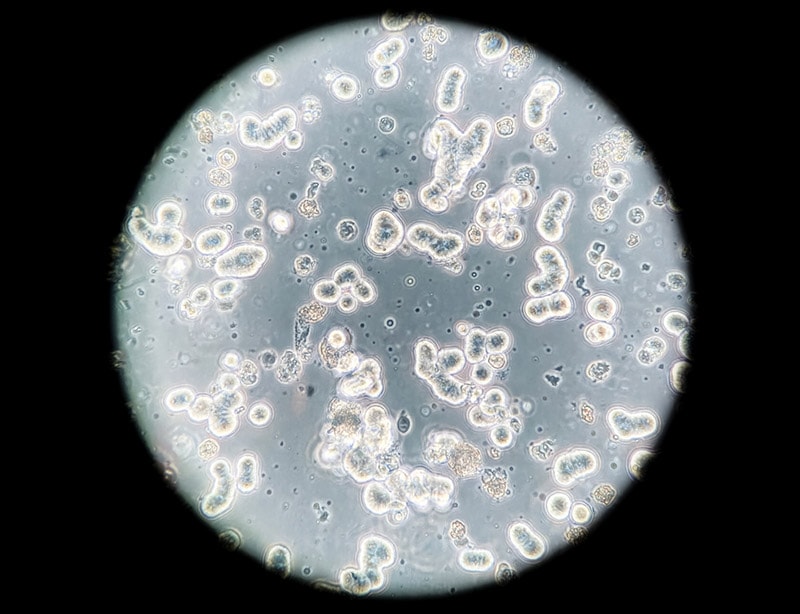

What Do Cells Look Like Under A Microscope Types Parts FAQ

What Do Cancer Cells Look Like Under A Microscope The Interesting